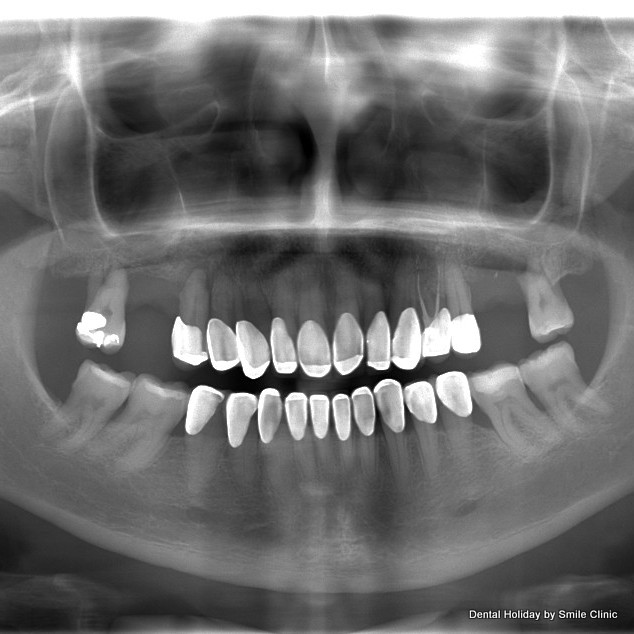

I arrived at the clinic in early December and after X-rays and scans were taken of my mouth by the clinic’s state of the art equipment I had a consultation with Dr. Marek. We sat down together and he clearly pointed out the bone-loss on either side of my upper jaw and confirmed my complaint that I felt the rest of my top teeth were loosening. He marked on the X-ray where he suggested he would place six implants on which to fix a permanent bridge of 14 teeth. I was very glad that he suggested 14 teeth instead of 12 teeth as I have a wide smile and would have been uncomfortable if it looked like my back teeth were missing.